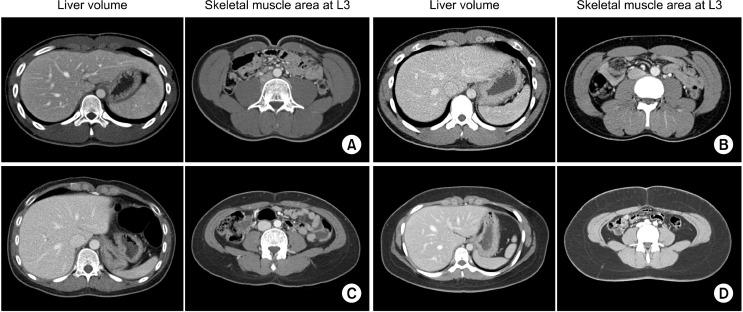

The study cohort was 500 hundred living liver donors who underwent surgery between January 2010 and December 2013. Computed tomography images were used for liver volumetry and skeletal muscle area measurement.

研究队列包括2010年1月至2013年12月期间接受手术的500名活体肝供者。计算机断层扫描图像用于肝脏容积测定和骨骼肌面积测量。